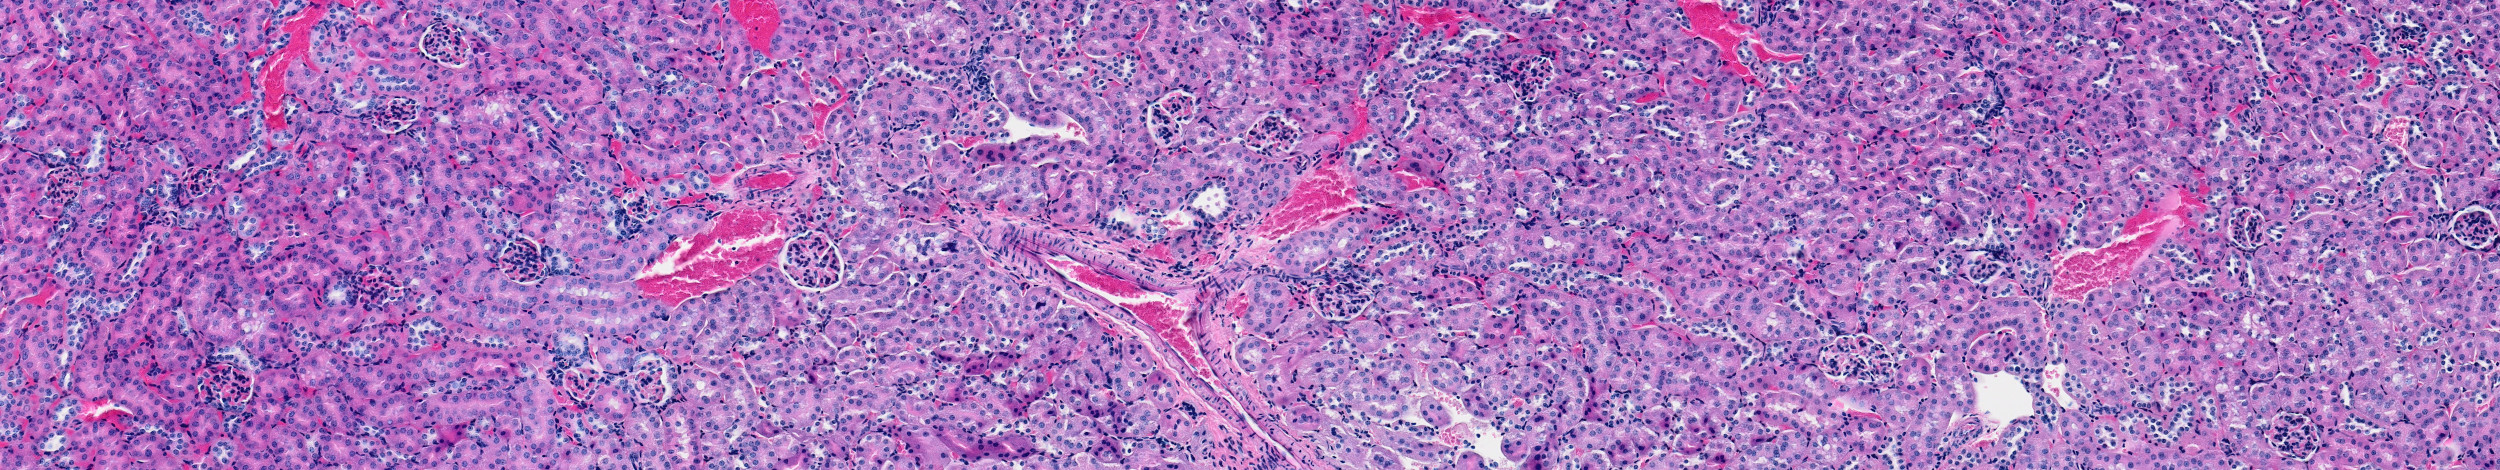

We aim to advance fundamental understanding of microchimerism and its role in human health and disease through the development and applications of phenotyping microchimeric cells and host immune systems. Our approach will allow us to characterize microchimerism in various tissues and environments, ranging from healthy pregnancies (mouse and human) to disease states (auto-immune diseases, pregnancy complications).

Microchimerism is the presence of cells from one individual in another genetically distinct individual.